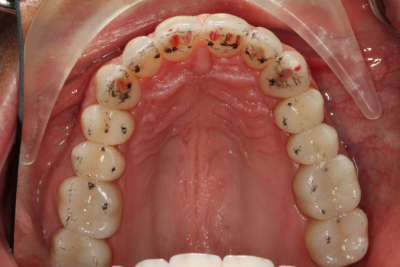

矯正治療後、私たちは間接修復のために上顎弓を準備し、ダレンに仮の修復物を装着しました。 また、下顎切歯縁をダイレクトコンポジットで修復し、露出した象牙質を封鎖し、診断用ワックスアップから製作した熱可塑性ステントを用いて切歯面を整えました。 ステントを使用して切縁にダイレクトコンポジットを装着することで、時間を節約し、切縁の位置をより正確にすることができました。 その後、ダレンは歯周病専門医に送られ、歯肉の構造を修正しました。

ダレンは、軟組織が完全に治癒するのを待つために、3ヶ月間プロビジョナルを装着したままにしました。 これにより、審美性、音声学、咬合、および機能を評価することもできました。

このケースでは、患者の機能包絡線と調和するように前方誘導を工夫しなければならなかったので、プロビジョナルは特に重要なものでした。 プロビジョナルレストレーションを装着した当初、ダレンは犬歯の位置と輪郭に「固定されている」と感じ続けていました。